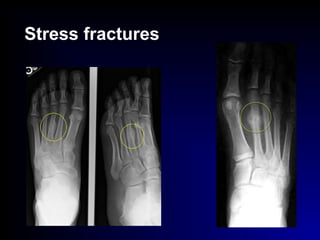

Stress fractures

 Stress fr.